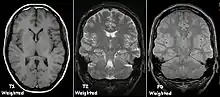

| Spin echo | T1 weighted | T1 | Measuring spin–lattice relaxation by using a short repetition time (TR) and echo time (TE). |

Standard foundation and comparison for other sequences |

| T2 weighted | T2 | Measuring spin–spin relaxation by using long TR and TE times |

Standard foundation and comparison for other sequences |

| Proton density weighted | PD | Long TR (to reduce T1) and short TE (to minimize T2).[7] | Joint disease and injury.[8]

Each tissue returns to its equilibrium state after excitation by the independent relaxation processes of T1 (spin-lattice; that is, magnetization in the same direction as the static magnetic field) and T2 (spin-spin; transverse to the static magnetic field). To create a T1-weighted image, magnetization is allowed to recover before measuring the MR signal by changing the repetition time (TR). This image weighting is useful for assessing the cerebral cortex, identifying fatty tissue, characterizing focal liver lesions, and in general, obtaining morphological information, as well as for post-contrast imaging. To create a T2-weighted image, magnetization is allowed to decay before measuring the MR signal by changing the echo time (TE). This image weighting is useful for detecting edema and inflammation, revealing white matter lesions, and assessing zonal anatomy in the prostate and uterus.

The standard display of MRI images is to represent fluid characteristics in black and white images, where different tissues turn out as follows:

| Signal | T1-weighted | T2-weighted |

|---|---|---|

| High |

|

|

| Inter- mediate | Grey matter darker than white matter[35] | White matter darker than grey matter[35] |

| Low |

|

|

Proton density

Proton density (PD)- weighted images are created by having a long repetition time (TR) and a short echo time (TE).[36] On images of the brain, this sequence has a more pronounced distinction between grey matter (bright) and white matter (darker grey), but with little contrast between brain and CSF.[36] It is very useful for the detection of arthropathy and injury.[37]